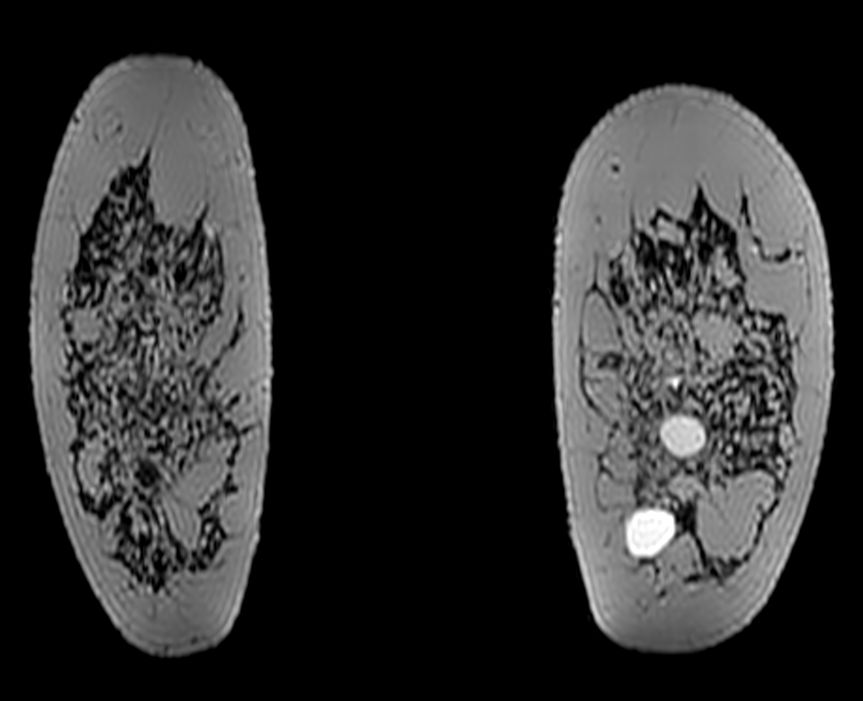

3D T2w BreastVIEW (coronal reformat)

3D VANE XD (coronal reformat)